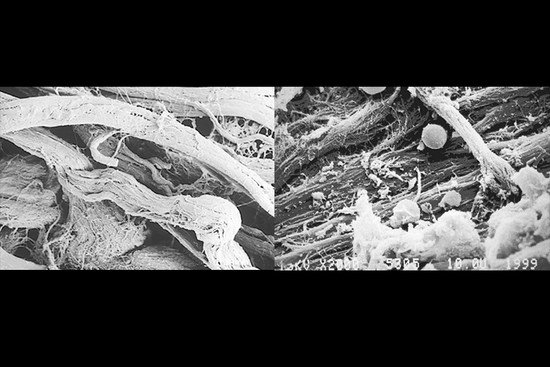

Geistlich Bio-Gide® Compressed ma taką samą unikatową, dwuwarstwową strukturę jak Geistlich Bio-Gide® (SEM, stained blue, 100x).

Wysokie (makrostrukturalne) podobieństwo Geistlich Bio-Gide® do ludzkiego kolagenu (SEM 2000x, Prof. Dr. Brenner).